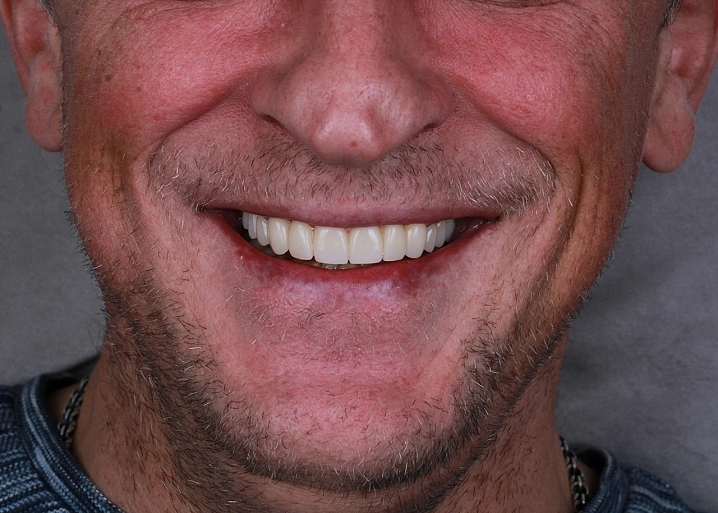

Специализация:

Восстановление зубов коронками и винирами, протезирование на имплантатах, изготовление съемных и несъемных протезов, решение проблем функциональности и эстетики зубочелюстной системы.